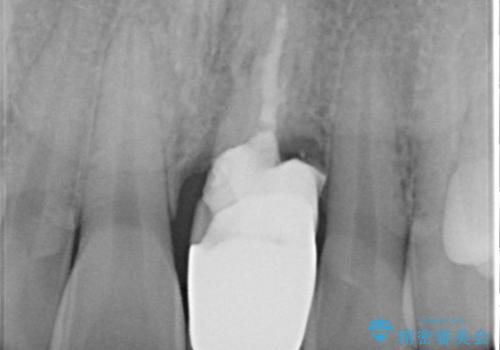

- 歯頚部外部吸収により抜歯適応の歯を抜歯して即時にインプラントを埋入したケースです。

インプラントの手術は二回になることが多いですが、1Dayインプラントの場合は手術は一回で済みます。